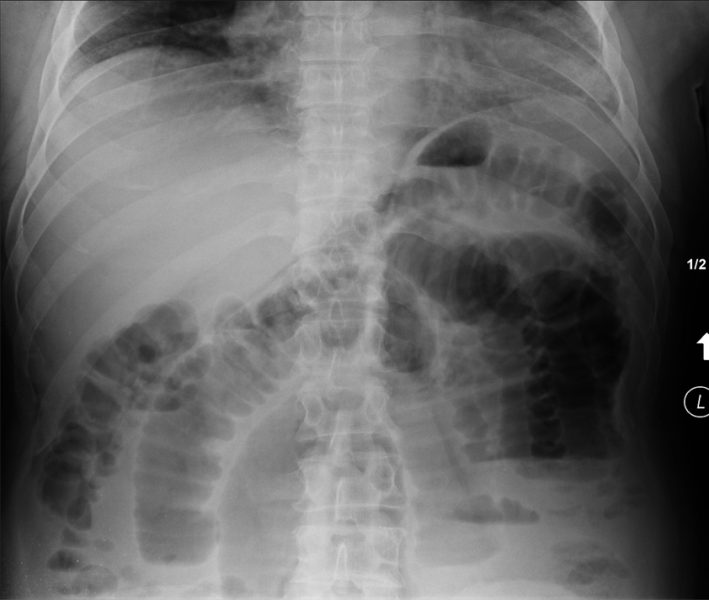

Nonspecific Bowel Gas Pattern. The interpretation nonspecific abdominal gas pattern should be avoided. Mild localized ileus or sentinel loop. Page Contents1 OVERVIEW2 ORIENTATIONS USED FOR ABDOMINAL X-RAYS3 ANATOMY ON ABDOMINAL X-RAY4 APPROACH GECkoS5 GAS PATTERN INTRALUMINAL6 EXTRALUMINAL GAS7 CALCIFICATIONS8 SOFT TISSUE MASSES OVERVIEW This page is dedicated to providing a guide on the approach to interpreting an abdominal X-ray. Posted 532012 330 PM GMT -7 Has anybody has this.

In patients with acute abdominal symptoms who have normal or abnormal but nonspecific bowel gas pattern on abdominal plain films CT is recom- mended see Fig. ICD-10-CM Diagnosis Code K59. Nonspecific bowel gas pattern. It is Non-Specific Bowel Gas Pattern. A physiological stool burden means you have a normal amount of stool in your colon. The radiology report is the primary means of communication between the radiologist and the referring physician.

Bowel gas patterns may point to an underlying cause bowel gas patterns include. This phrase is often used when the bowel gas pattern is not specific for a small bowel obstruction. Small bowel air usually appears as multiple small randomly distributed gaseous foci scattered throughout the abdomen. I suggest you look the article by. Emergency R a d i o l o g y M a y J u n e 1996 further.

The bowel gas pattern is normal. It is Non-Specific Bowel Gas Pattern. Infectious Disease 33 years experience. This doesnt help the ordering physician much except to tell him to use his clinical suspicion to guide further workup. Page Contents1 OVERVIEW2 ORIENTATIONS USED FOR ABDOMINAL X-RAYS3 ANATOMY ON ABDOMINAL X-RAY4 APPROACH GECkoS5 GAS PATTERN INTRALUMINAL6 EXTRALUMINAL GAS7 CALCIFICATIONS8 SOFT TISSUE MASSES OVERVIEW This page is dedicated to providing a guide on the approach to interpreting an abdominal X-ray.

Dilatation 3cm of the small bowel is considered abnormal however the longer the segment of bowel that is dilated the more likely bowel dilatation represents a genuine obstruction. Functional disorders of stomach K31- ICD-10-CM Diagnosis Code K59. Change in bowel habit NOS R194. Im only addressing the first question. Nonspecific bowel gas pattern.

X-ray The bowel gas pattern appears unremarkable. It basically means that the appearance of bowel is unclear on the X-ray and can be normal or abnormal. Page Contents1 OVERVIEW2 ORIENTATIONS USED FOR ABDOMINAL X-RAYS3 ANATOMY ON ABDOMINAL X-RAY4 APPROACH GECkoS5 GAS PATTERN INTRALUMINAL6 EXTRALUMINAL GAS7 CALCIFICATIONS8 SOFT TISSUE MASSES OVERVIEW This page is dedicated to providing a guide on the approach to interpreting an abdominal X-ray. ICD-10-CM Diagnosis Code K59. See the page on normal Bowel Gas Pattern.

Slide 2 of 3. A normal small bowel gas pattern varies from no gas being visible to gas in three or four variably shaped small intestinal loops. NSBGP is a shorter form of Non-Specific Bowel Gas Pattern. Nonspecific bowel gas pattern. We all have gas in our bowels and a non obstructive bowel gas pattern means it looks like it should look.

K59 Other functional intestinal disorders. Non-Specific Bowel Gas Pattern - How is Non-Specific Bowel Gas Pattern abbreviated. K59 Other functional intestinal disorders. The term nonspecific abdominal gas pattern should be abandoned because it may signify a normal condition or a pathologic state. Small bowel obstruction - features.

A normal small bowel gas pattern varies from no gas being visible to gas in three or four variably shaped small intestinal loops. In patients with acute abdominal symptoms who have normal or abnormal but nonspecific bowel gas pattern on abdominal plain films CT is recom- mended see Fig. Monocular exotropia of left eye with a pattern ICD-10-CM Diagnosis Code H50122 Monocular exotropia with A pattern left eye. This type of scan is also sometimes. The bowel gas pattern is normal.